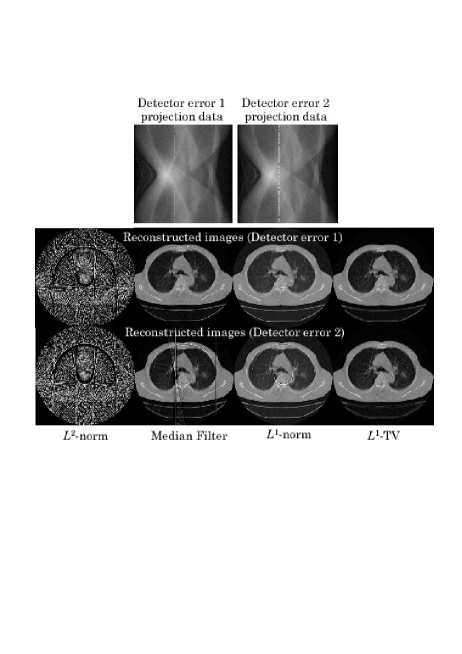

[Scenario 1](Detector Errors) Two cases were simulated. In the first case, projection data bins corresponding to two detector elements were contaminated with the abnormal errors (Detector Error 1). In the second case, projection data bins corresponding to two adjacent detectors were contaminated with the abnormal errors in two different locations (Detector Error 2).

In all the scenarios, we used a single transaxial slice of chest CT scan image consisting of 320320 pixels. The simulated projection data was computed with the sampling of 320(angles)320(radial bins), from which an image consisting of 320320(pixels) was reconstructed. We have compared the following four different algorithms.

[-Norm Reconstruction] The -norm reconstruction of Eq. (22) was implemented with the iteration number 50.

[Projection Space Median Filter] This is an empirical method to remove the effect of abnormal errors. The median filter is applied to degraded projection data to remove the abnormal errors followed by the -norm reconstruction. The window size of median filter was empirically determined in such a way that visual quality of reconstructed image is best dependent on each case.

[-Norm Reconstruction] The -norm reconstruction (Algorithm 2) was implemented with the iteration number 50.

[-TV Reconstruction] The -TV reconstruction (Algorithm 3) was implemented with the iteration number 50.

We show reconstructed images together with the degraded projection data for all the scenarios in Figs. 3-5. In all the scenarios, the images by the -norm reconstruction were severely damaged by the abnormal errors, in which the artifact patterns, i.e. streaks, random errors, etc., depend on the locations of abnormal bins. The empirical projection space median filtering succeeded in reducing the artifacts, but the filtering also affects the correct data so that we can observe some additional artifacts in the final images. On the other hand, for the cases of Detector Error 1, Angle Error 1, and Random Error 1 with relatively mild errors, the power of identifying the abnormal bins in both the -norm and -TV reconstructions were significant in which they succeeded in reconstructing almost perfect images. However, the difference between the -norm reconstruction and the -TV reconstruction became apparent for the more difficult cases of Detector Error 2, Angle Error 2, and Random Error 2. In these cases, the -TV reconstruction correctly identified most of the abnormal bins whereas the -norm reconstruction did not succeed perfectly. With respect to convergence speed of the -norm and -TV reconstructions, they were a bit slower compared with the -norm reconstruction and the standard ART algorithm mainly because early iterations need to be spent to correctly identify the locations of abnormal bins. However, thanks to their row-action structures, they seem to be still significantly faster than using the standard -norm and -TV minimization algorithms (for example, popular iterative reweighted least-squares method [3],[4]) which can be used for the same cost functions.